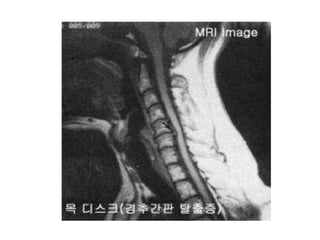

COLUNA CERVICAL

C1 – Atlas

C2 – Axis

C3 a C7: Corpo, arco neural posterior,

lâmina, pedículos, processos transversos

e espinhosos.

PROTOCOLO